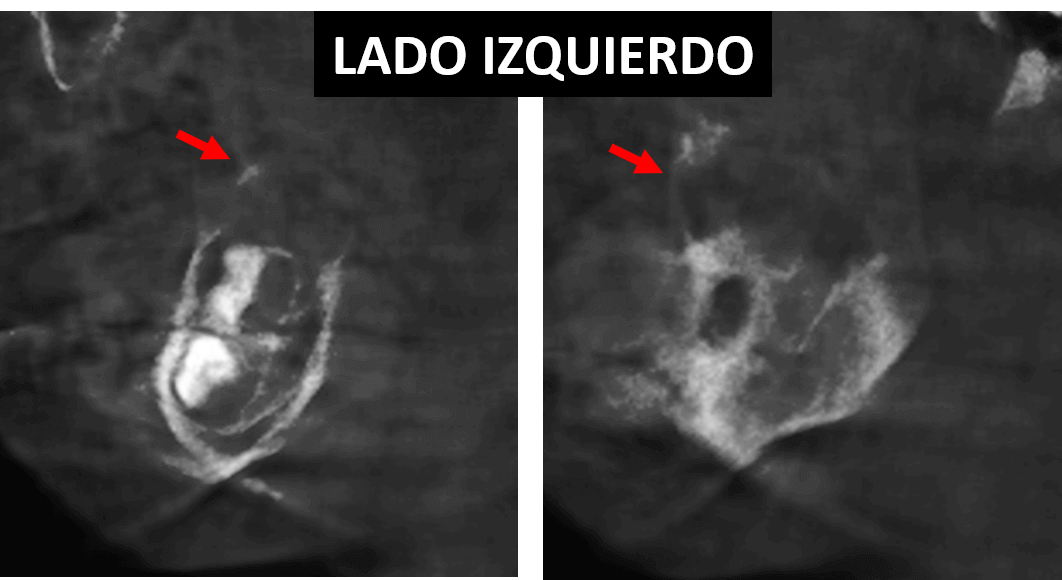

Fig.2

En cortes coronales (Fig.2) se observan ambas lesiones osteolítica se observa el compromiso de las tablas óseas en ambas ramas ascendente. Nótese que la lesión del lado derecho supera en volumen a la lesion contralateral.